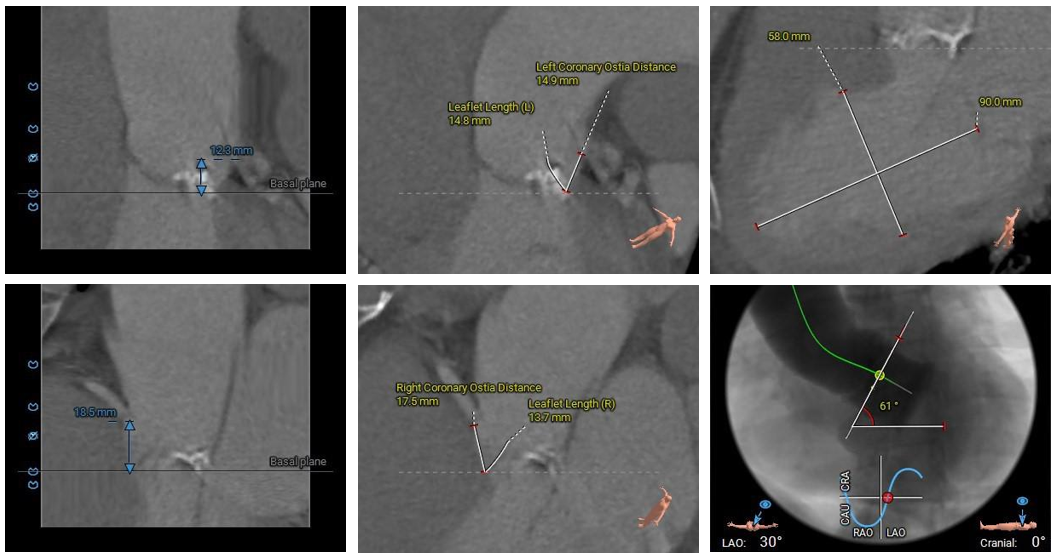

术前CT评估

• Type1型二叶式主动脉瓣,L-R间可见钙化融合脊,瓣叶增厚伴中度钙化,钙化主要分布于左冠瓣叶边缘及左无交界处,左室流出道呈敞口型;

• 左右冠开口高度尚可,切线位测量未见冗长瓣叶;冠脉未见钙化斑块;

• 瓦氏窦、窦管交界内径尚可,升主动脉扩张;左室腔内径偏大,心室壁厚度尚可;

• 瓣环水平夹角为61°,主动脉弓距及弓部夹角偏小;降主动脉扭曲折叠成角;

主动脉根部测量

瓣上结构测量

冠脉阻挡风险、左室大小及横位心评估